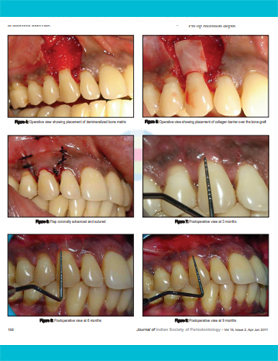

Periodontal Tissue Regeneration (2019)

OSSEOGRAFT ® (DMBM - Xenograft)

&HEALIGUIDE ® (Bioresorbable GTR/GBR Membrane)